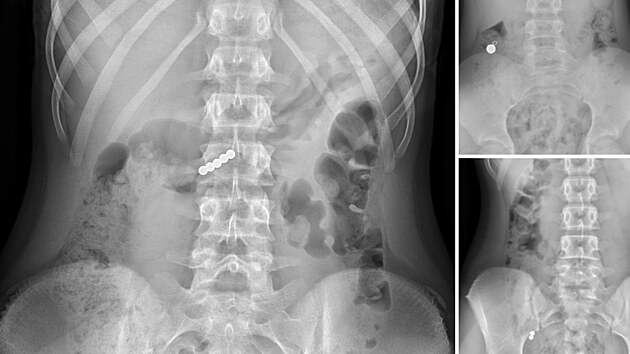

„Při spolknutí více magnetů nebo magnetu a kovového předmětu hrozí jejich spojení, které může k sobě přitáhnout například žaludek a střevo a způsobit jeho poškození, nebo i dokonce proděravění,“ uvedli zástupci nemocnice.

„Pak omylem došlo k polknutí těchto kuliček. Jedna pacientka měla velké štěstí a kuličky vyšly bez problémů, další pacienti ale v současné době zůstávají hospitalizováni,“ uvedla nemocnice.